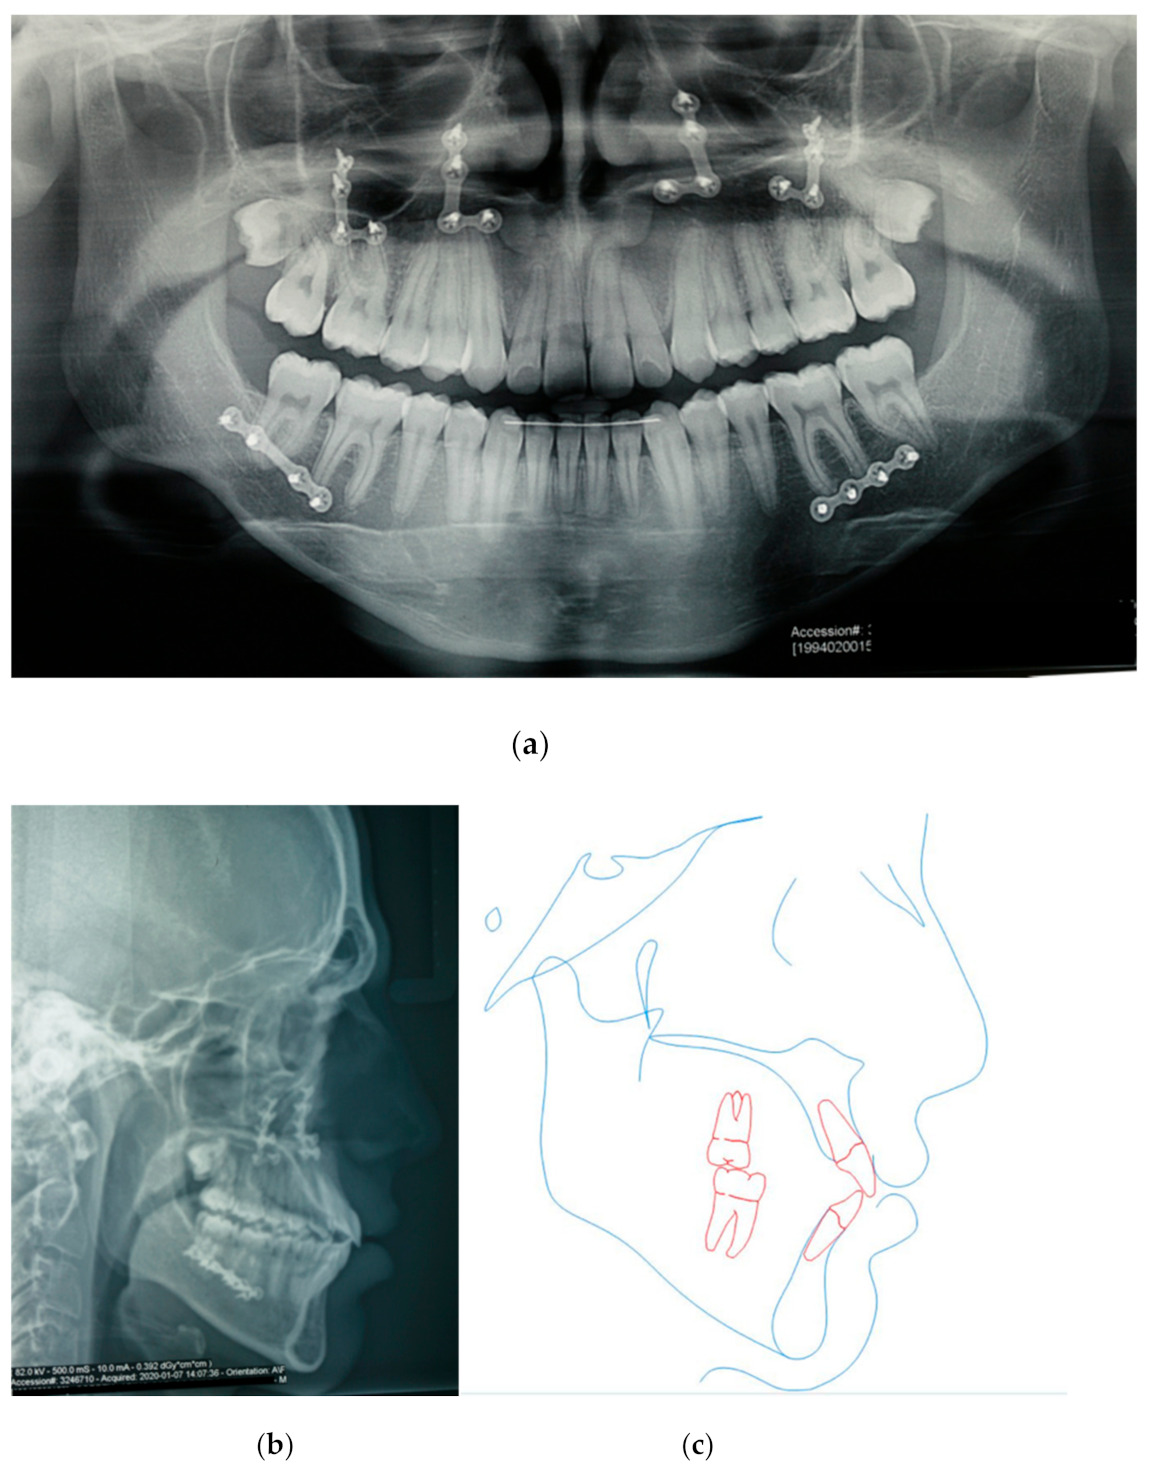

3.1. The Presurgical Orthodontic Treatment

3.2. Orthognathic Surgery